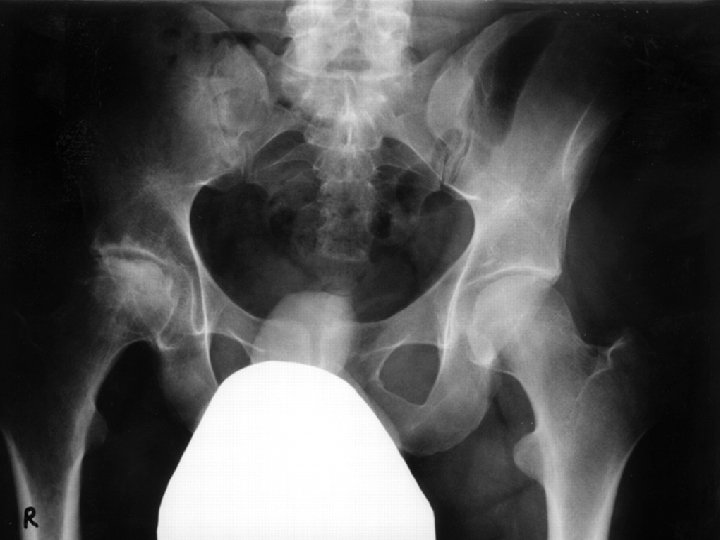

Case 2 • 43 yo F with long standing history of “asthma” • Wheeze and shortness of breath with exercise and stress • Treated with maximum dose ICS • Has received multiple prednisone courses • Presents to you, Cushingoid • Inspiratory wheeze